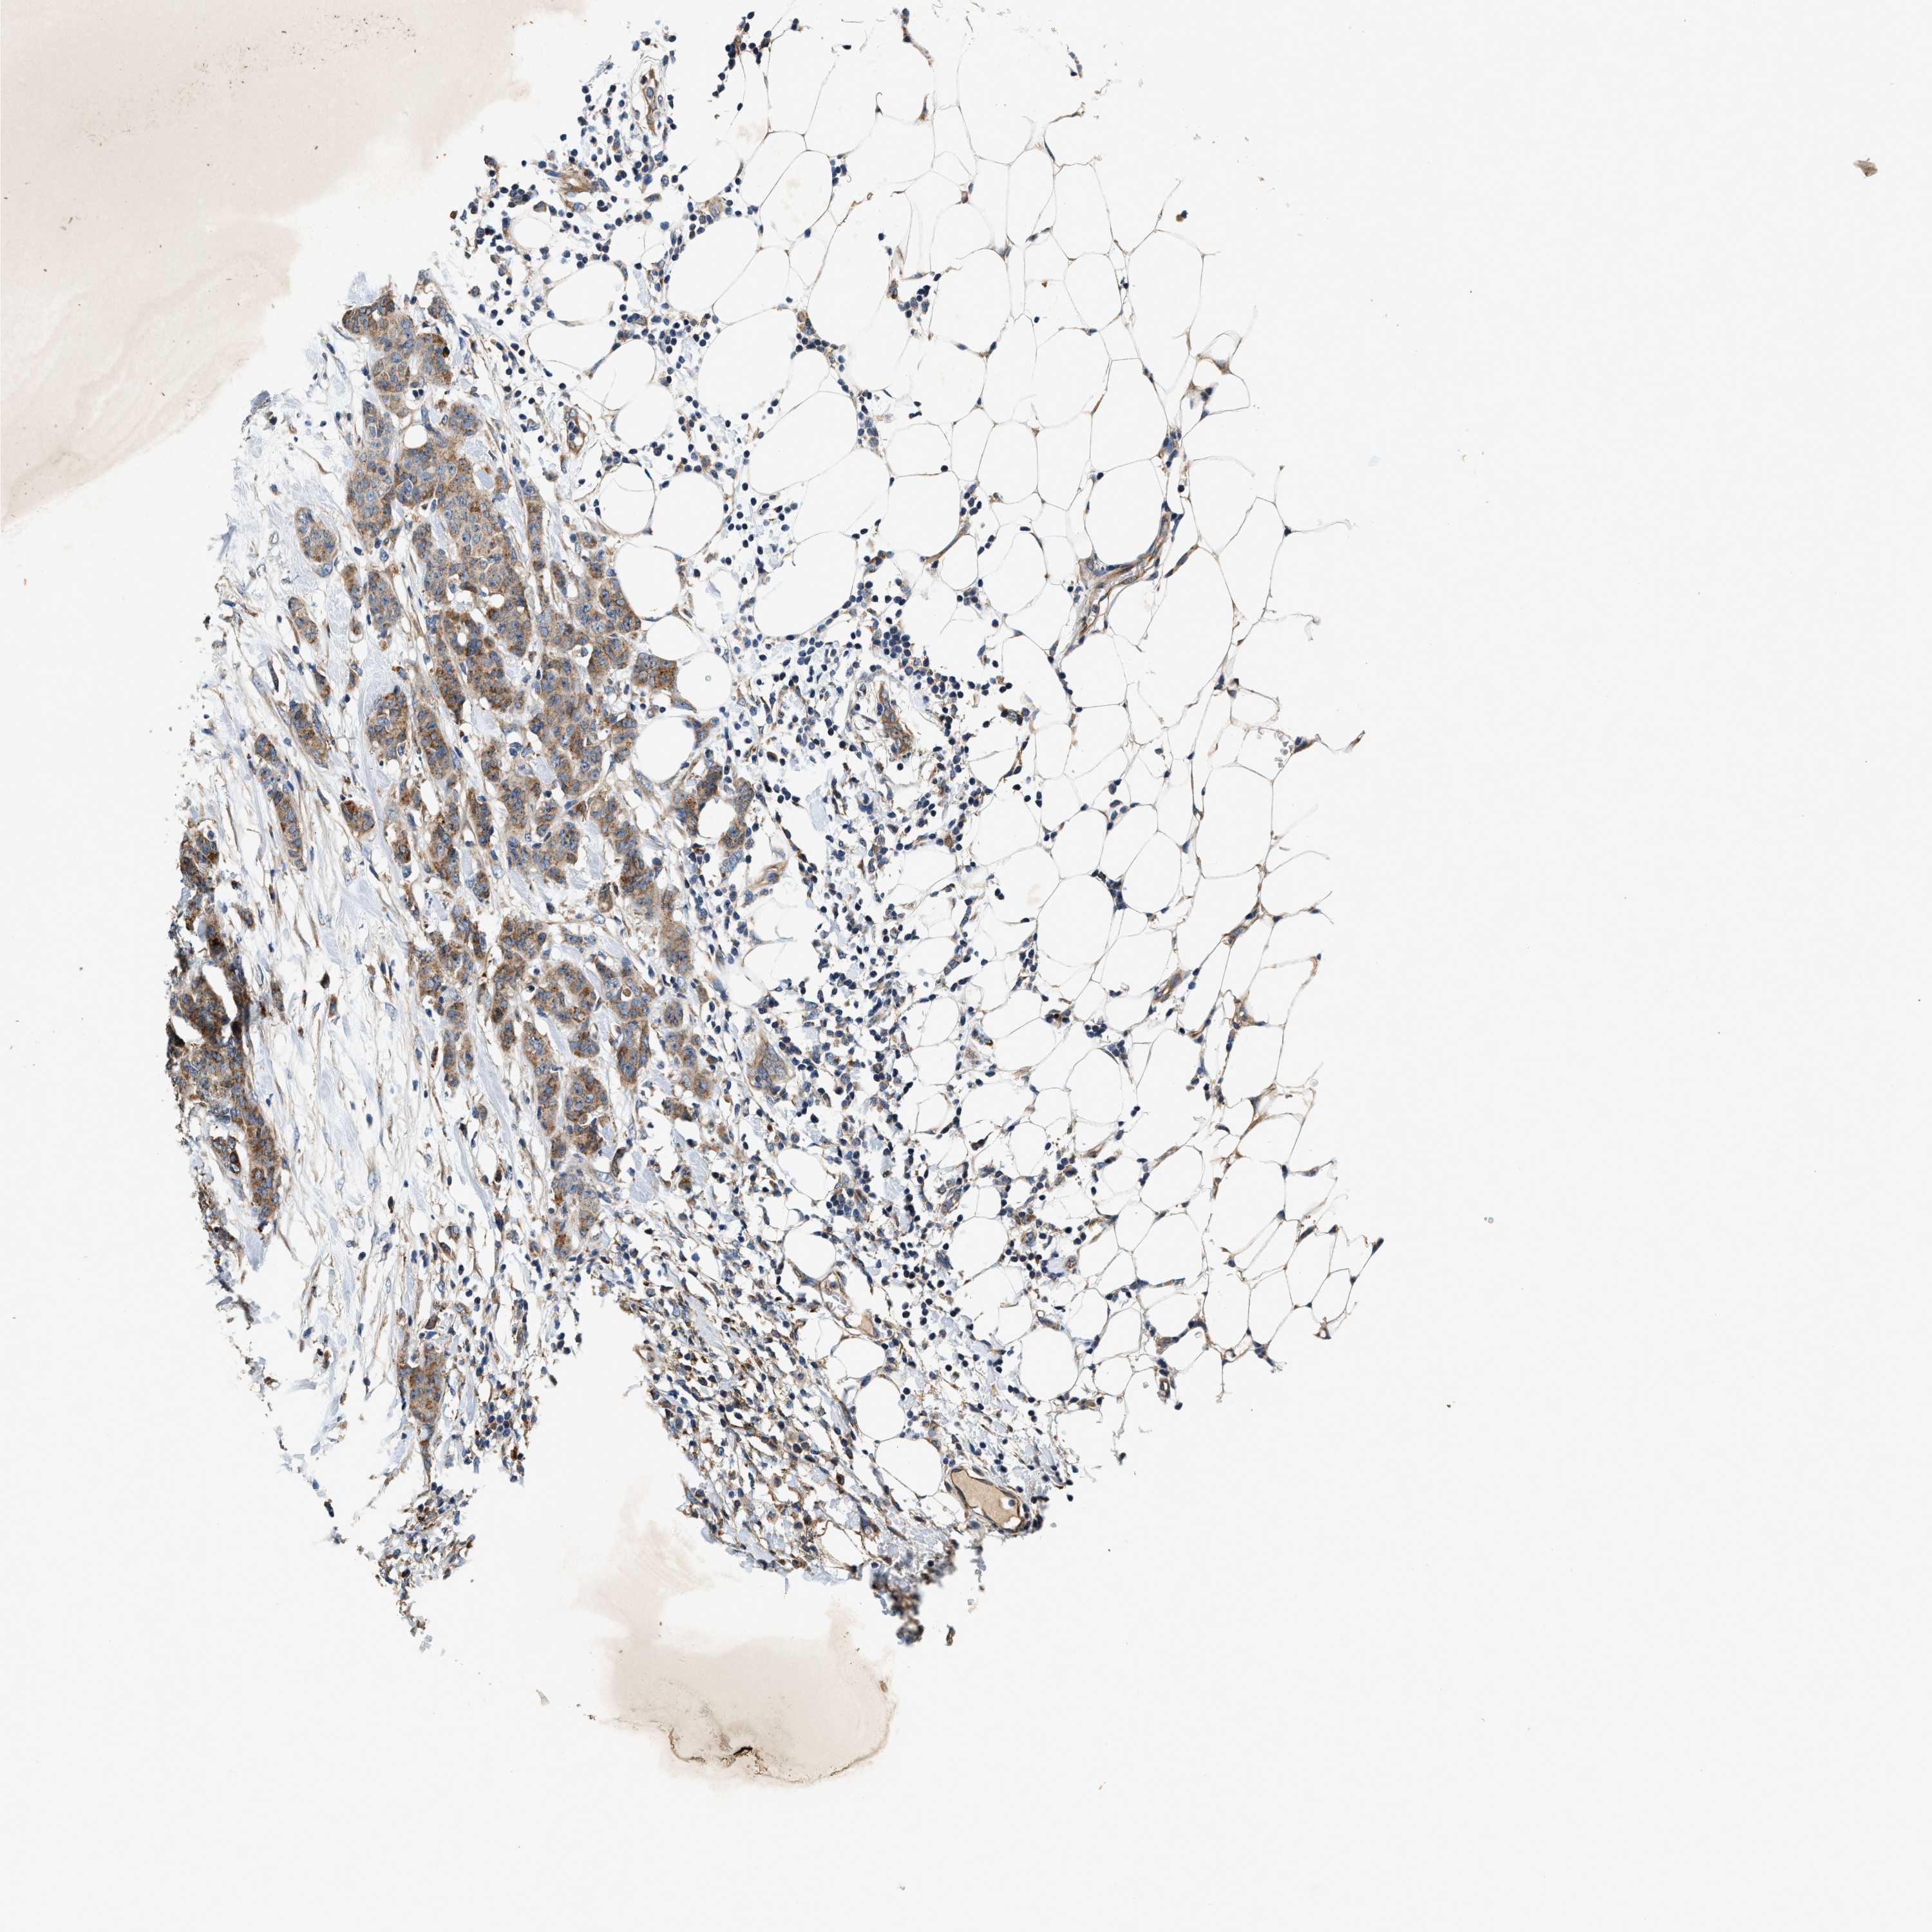

CANCER BREAST CANCER Show tissue menu

BRCA TCGA BRCA VALIDATION PROTEIN EXPRESSION